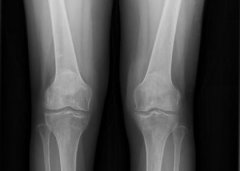

• 风湿患者治疗后关节肿痛症状消失

强女士是一位医院退休护士,来自西藏拉萨市,患者自4+前出现双手 ...

吴女士20+年前出现双手、双足、双小腿疼痛不适,曾在当地医院就 ...